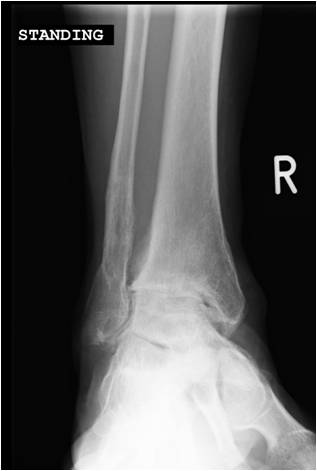

Degenerative arthritis of the ankle joint (Fig 1) normally develops as a result of a traumatic injury, but can also present from inflammatory joint disease such as rheumatoid arthritis and other rare conditions. Common symptoms are pain, swelling and stiffness interfering with walking and other activities.